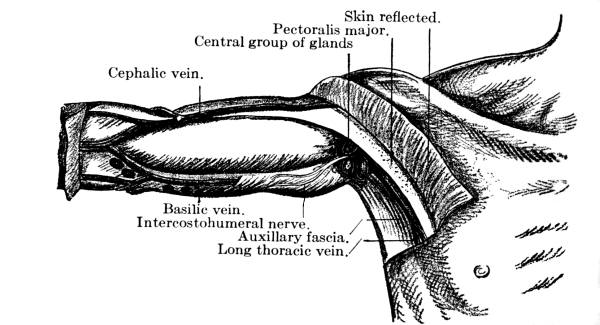

Fig. 9.—Central (superficial) lymphatic glands of the axilla. (After Leaf.)

The lymphatic glands are small oval glandular bodies and occur here and there along the course of the lymphatics. Before entering one of them the vessel breaks up into several afferent vessels which form a plexus within and then emerge again as several efferent vessels which soon unite to form one trunk. These glands occur chiefly in the mesentery, along the great vessels, and in the mediastinum, axilla, neck, elbow, groin, and popliteal space.

The lymph glands serve as a protection to adjacent parts and when it leaves the gland the lymph is purer and richer in leucocytes than when it entered. In fact, they filter harmful matter from the lymph and apparently also form white corpuscles. Normally they can with difficulty be felt, but in disease, if the leucocytes are unable to destroy or carry off the poison, the lymph carries it along to the glands, which swell and become tender. If the infection is not severe the swelling goes down and the tenderness passes after a short time, but if it is severe, there may be suppuration and abscess formation and [Pg 35] the gland even perhaps be destroyed, giving its life for the health of the part. Thus a wound in the foot, if infected, may cause irritation and enlargement of the glands at the knee and in the groin.

The lymphatic glands are frequently the seat of tubercular infection, especially in the neck, and are enlarged in scarlet fever, tonsillitis, and diphtheria. In syphilis there is general glandular enlargement, and the glands in the groin become enlarged in all diseases of the genital organs. In malignant growths, such as cancer, the extension of the disease is often along the lines of the lymphatics.